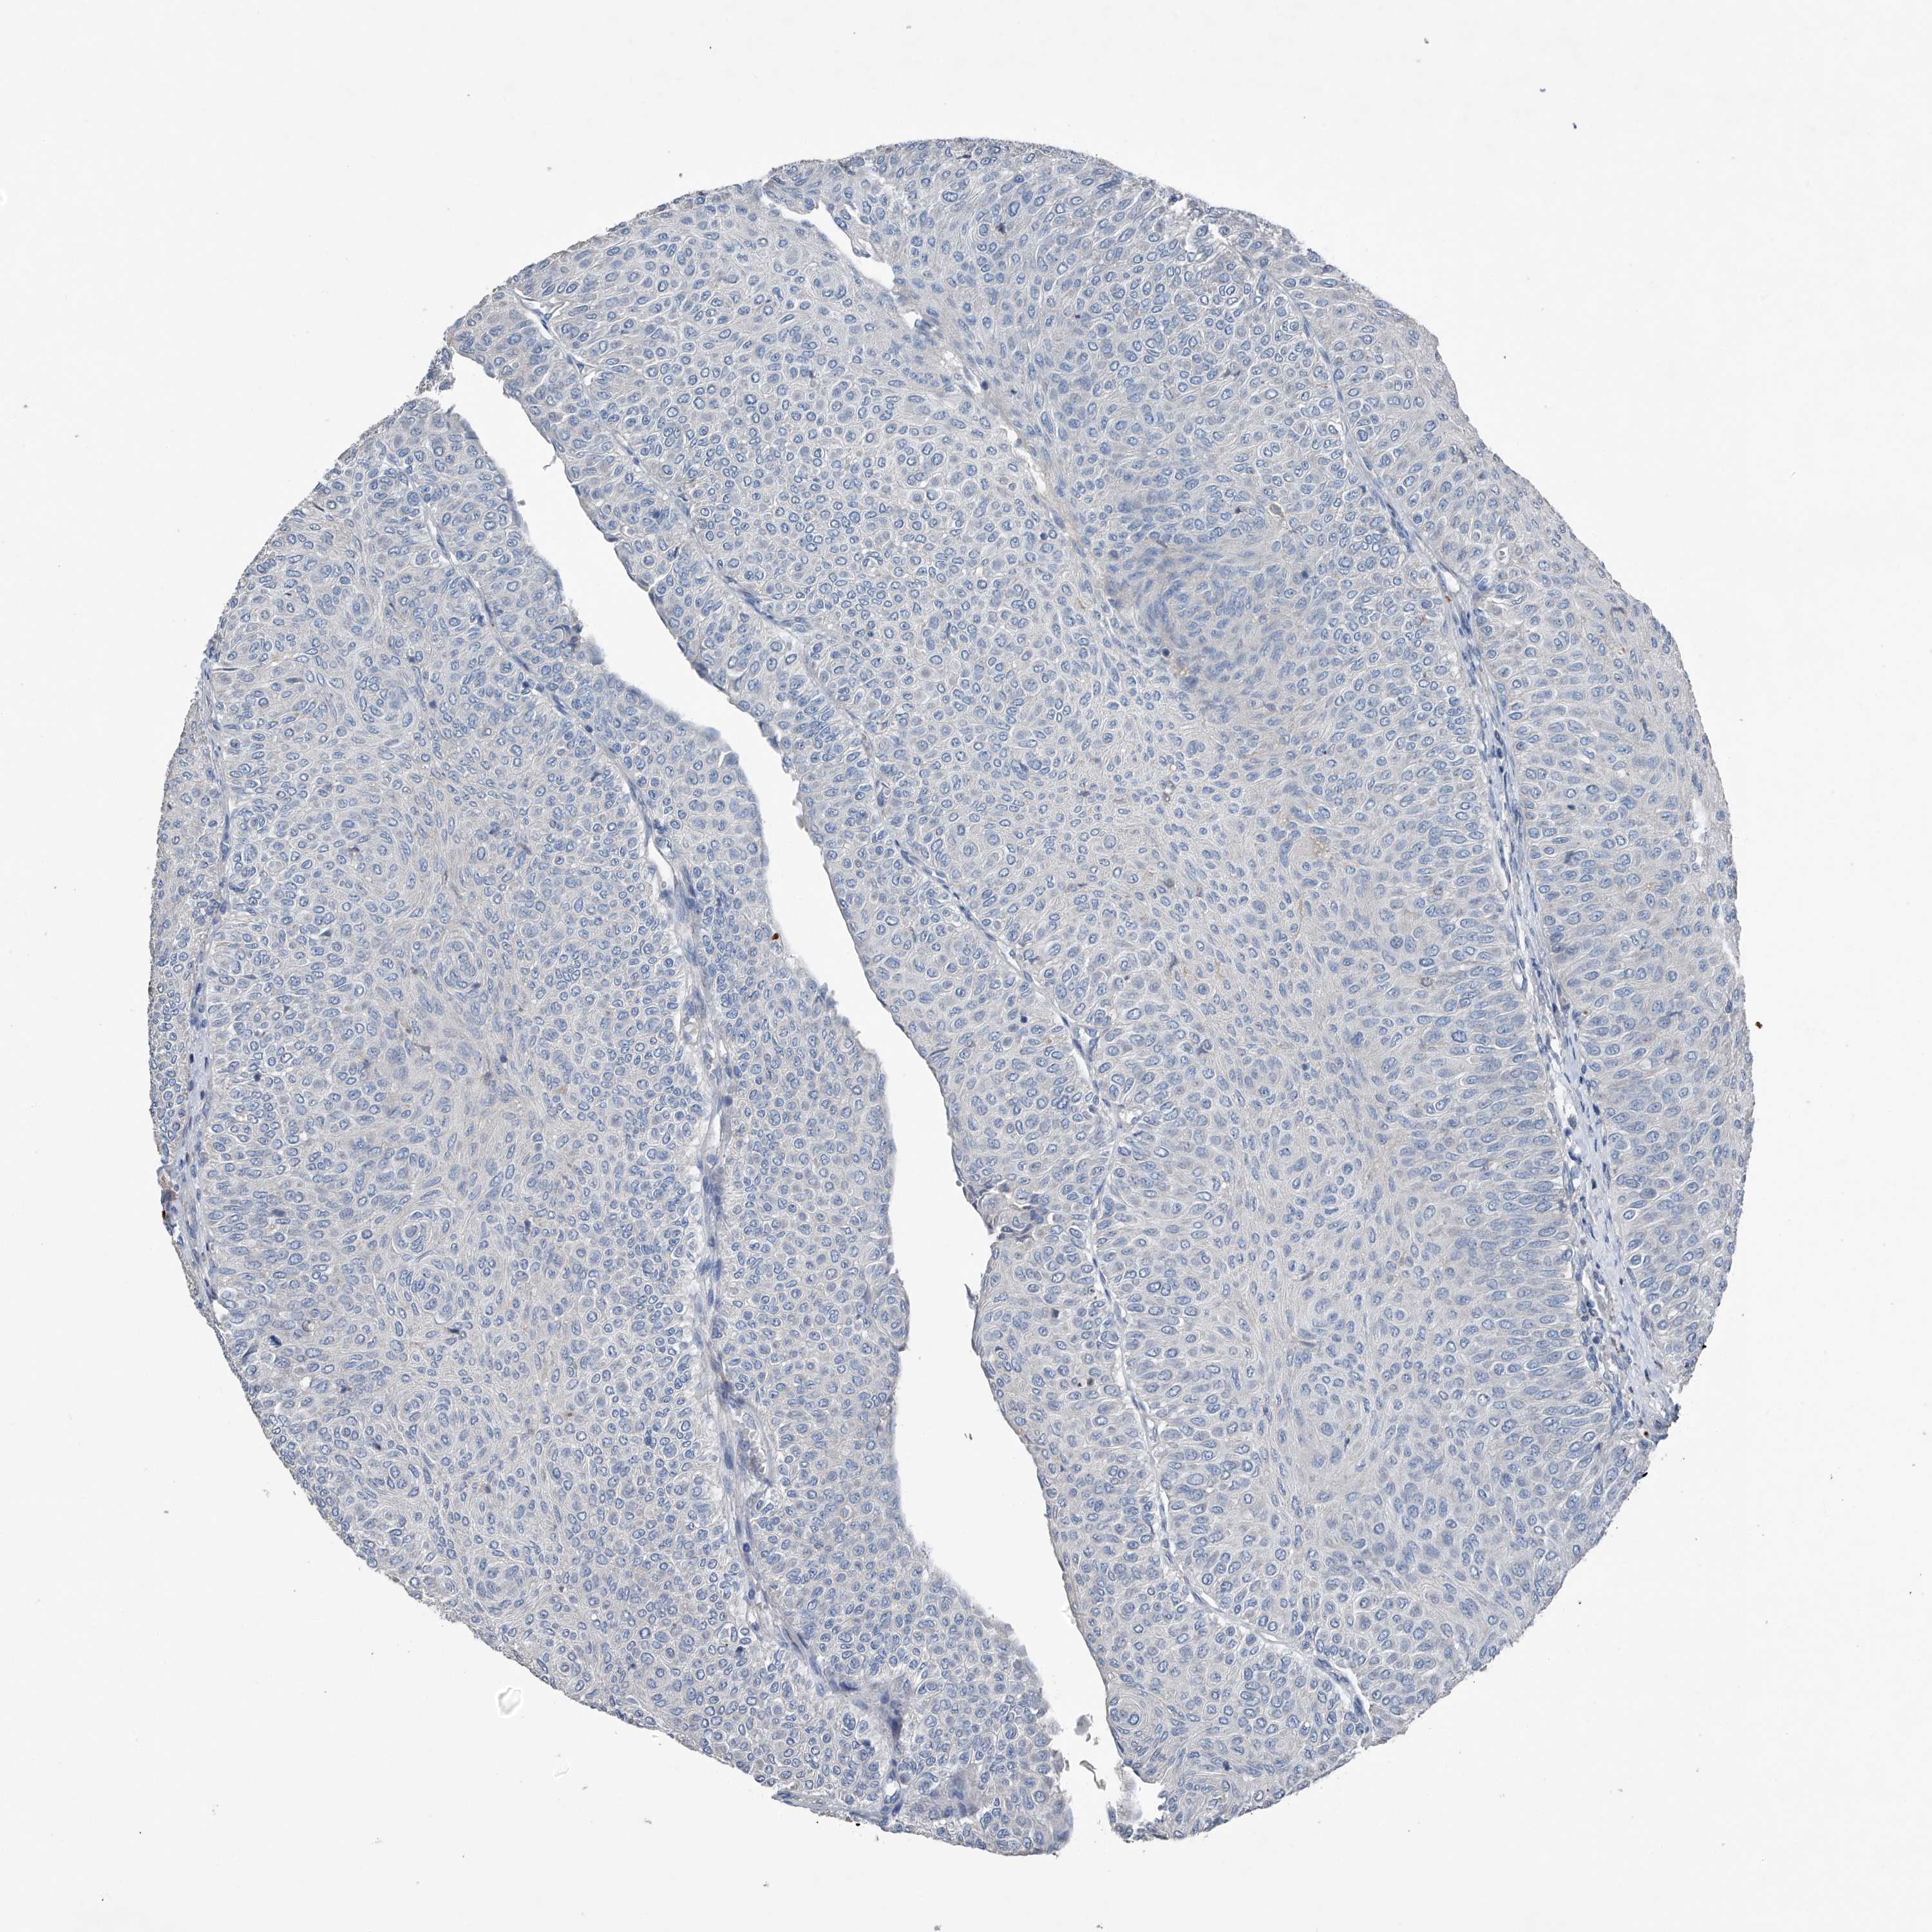

UROTHELIAL CANCER - Protein expressioni

A mouse-over function shows sample information and annotation data. Click on an image to view it in a full screen mode. Samples can be filtered based on level of antibody staining by selecting one or several of the following categories: high, medium, low and not detected. The assay and annotation is described here.

Note that samples used for immunohistochemistry by the Human Protein Atlas do not correspond to samples in the TCGA dataset.

Antibody stainingi

Antibody staining in the annotated cell types in the current human tissue is reported as not detected, low, medium, or high, based on conventional immunohistochemistry profiling in selected tissues. This score is based on the combination of the staining intensity and fraction of stained cells.

Each image is clickable and will lead to virtual microscopy that enables deeper exploration of all samples and also displays staining intensity scores, fraction scores and subcellular localization as well as patient and tissue information for each sample.

Antibody HPA031312

Staining

High

Medium

Low

Not detected

Intensity

Strong

Moderate

Weak

Negative

Quantity

>75%

75%-25%

<25%

None

Location

Nuclear

Cytoplasmic/membranous

Cytoplasmic/membranous,nuclear

Urothelial carcinoma, Low grade

Urothelial carcinoma, High grade